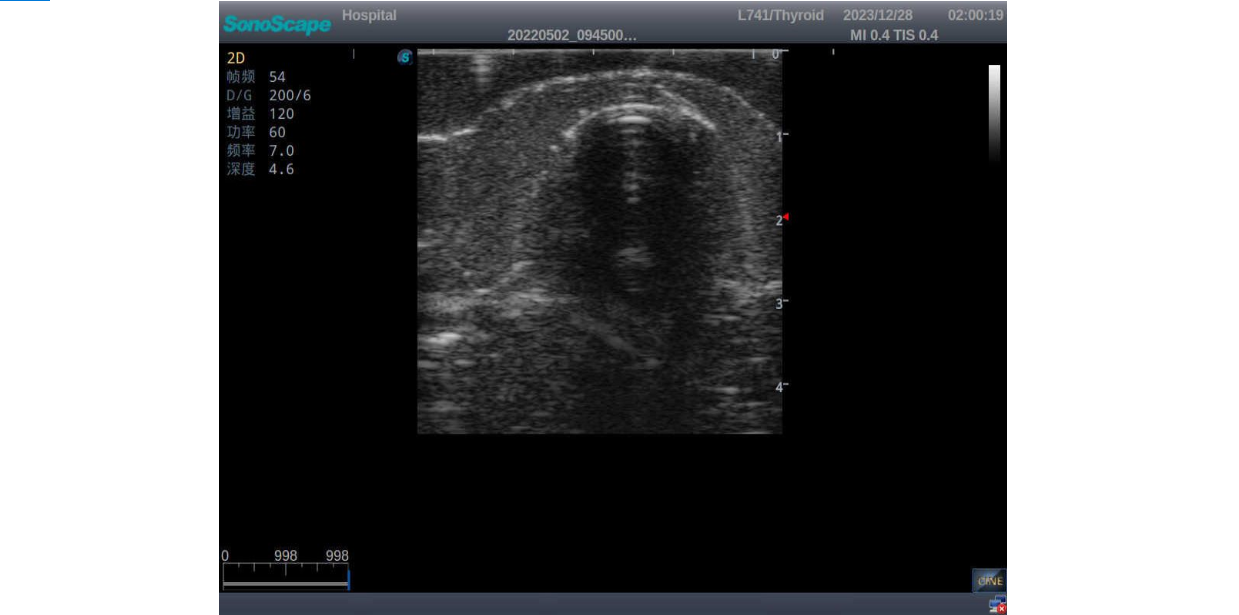

Thyroid Ultrasound Training Model

ModelTYE1595

This product has true-to-life male torso including head, neck, shoulder and upper chest. It serves as an excellent teaching tool for identification of various types of normal thyroid, thyroid adenoma, thyroid cancer, nodular goiter, thyroid cyst and training on proper thyroid scanning techniques.

3)       It comes with four (4) thyroid modules and can show five (5) ultrasonic images: normal thyroid, thyroid adenoma, thyroid cancer, nodular goiter, thyroid cyst

Normal thyroid with homogeneous parenchymal echo and well-defined capsule

Thyroid adenoma with well-defined border and smooth uniform halo

Thyroid cancer with irregular mass, unclear border, uneven internal echo or calcification strong echoes

Nodular goiter with irregular border and varying sizes of low echo, isoechoic, or high echo nodules

Thyroid cyst, which fluid area, dark and echo-free area can be seen